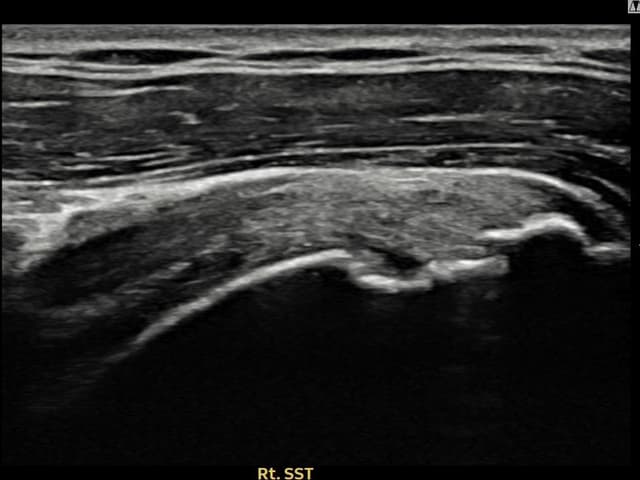

右侧 冈上肌腱 石灰化肌腱炎

10mm × 7mm